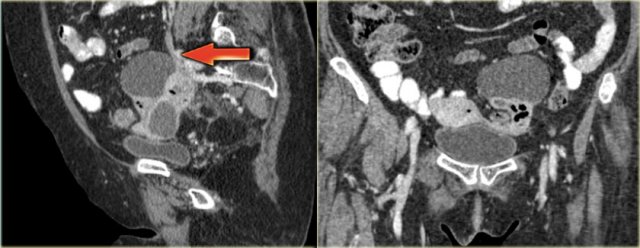

The axial CECT image shows a left complex cystic lesion with thick enhancing walls and internal gas.

It looks like an abscess.

Note the relatively unremarkable aspect of the overlying mesentery: this is unlikely to be a peri-diverticular abscess.

Continue with the reconstructed images.

On the sagittal image notice, that the lesion is connected to the ovarian vein confirming that this is an ovarian lesion (arrow).

The coronal image shows the anatomic connection to the uterus.

There is a gasbubble in the uterine cavity, which confirms the suggestion of an infection rising from the uterine cavity via the salphinx to involve the ovary (click or tap the image to enlarge).